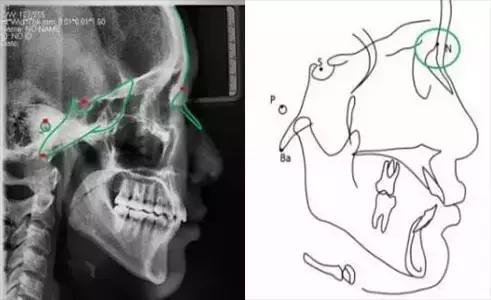

标志点是用来构成一些平面及测量内容的点。理想的标志点应该是易于定位的解剖标志,在生长发育过程中应相对稳定。但并不是常用的标志点均能符合这一要求,不少标志点的确定是由各学者提出的不同测量方法而定,而标志点的可靠性还取决于头颅X线片的质量以及描图者的经验。

头影测量标志点可分为两类:一类是解剖的,这一类标志点是真正代表颅骨的一些解剖结构;另一类是引伸的,这一类标志点是通过头影图上解剖标志点的引伸而得,如两个测量平面相交的一个标志点。

颅部标志点

蝶鞍点(S.sella):蝶鞍影像的中心。这是常用的一个颅部标志点,在头颅侧位片上较容易确定。

鼻根点(N.nasion):鼻额缝的最前点。这是前颅部的标志点,代表面部与颅部的结合处。有些X线片上,此点显示不太清楚,是因为其形态不规则骨缝形成角度之故。

耳点(P.porion):外耳道之最上点。头影测量上常以定位仪耳塞影像之最上点为代表,称为机械耳点。但也有少数学者使用外耳道影像之最上点来代表,则为解剖耳点。

颅底点(Ba.basion):枕骨大孔前缘之中点。一般此点较易确定,常作为后颅底的标志。

Bolton点:枕骨髁突后切迹的最凹点。